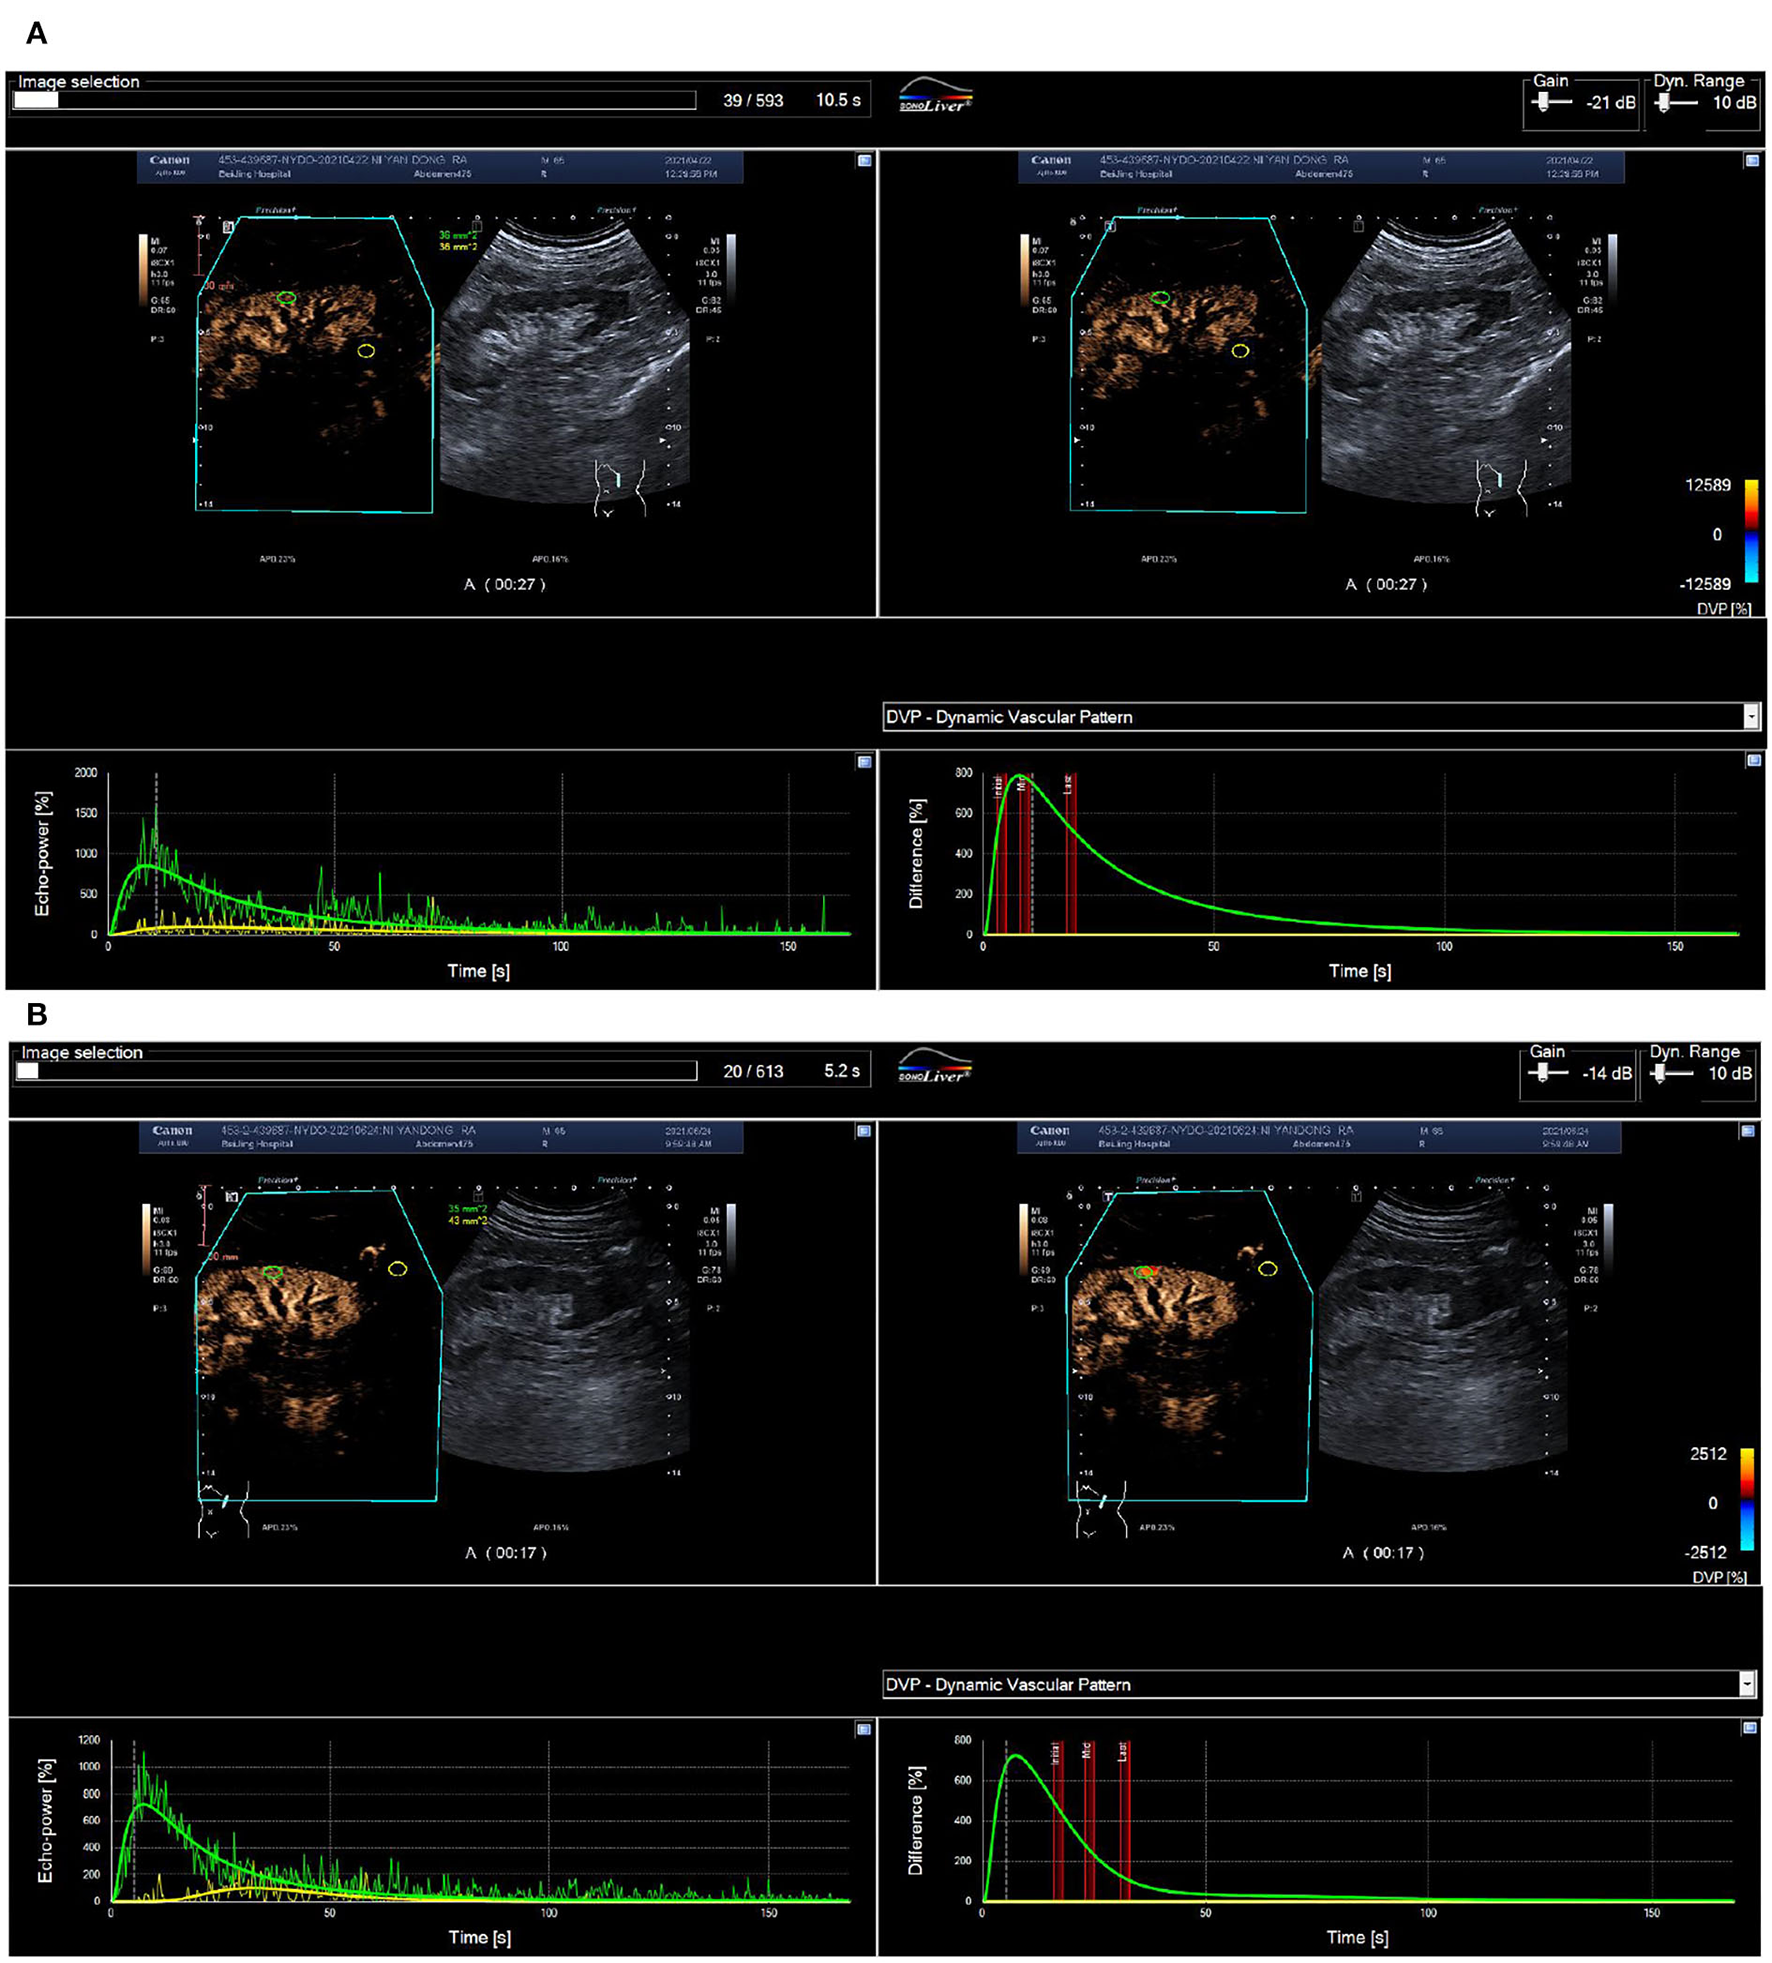

After stent implantation, the BP nonresponse group was associated with significantly reduced RT (P < 0.05), but other CBP parameters (IMAX, TTP, mTT, AUC1, and AUC2) did not change significantly (P > 0.05) (Figure 2). In the BP response group, IMAX, AUC1, and AUC2 were significantly increased, while the RT and mTT were significantly shortened (P < 0.05), and TTP was significantly prolonged compared with pre-operation (P < 0.05) (Table 2).

Figure 2

Routine ultrasound and CEUS images of a 65-year-old man with 70% right renal ostial stenosis. (A) Color Doppler flow (left), Doppler frequency spectrum (middle), and CEUS (right) images of the long axis section of right renal artery before PTRAS. (B) After stent implantation, renal artery blood flow images (left) and the peak systolic velocity (middle) of stenosis were corrected, and contrast beam filling (right) displayed normal. RA, renal artery; AO, abdominal aorta. (A) Pre-operative cortical blood perfusion, IMAX (%): 855.1, RT (s): 7.7, TTP (s): 8.3, mTT (s): 42.5, AUC1: 47.5, AUC2: 308.4; (B) Post-operative cortical blood perfusion, IMAX (%): 725.3, RT (s): 6.7, TTP (s): 7.3, mTT (s): 27.9, AUC1: 34.6, AUC2: 194.4. Changes in cortical blood perfusion before (A) and after (B) stent implantation of a 57-year-old woman with severe stenosis of the right renal artery in the BP nonresponse group.

After stent implantation, compared with the BP nonresponse group, the CBP of the BP response group was significantly different, manifested as a significant increase in IMAX, AUC1, and AUC2, and an increase in RT, mTT, and TTP (P < 0.05) (Figures 2, 3).

Figure 3

ROC curve of renal blood perfusion parameters for predicting poor prognosis. (A) Pre-operative cortical blood perfusion, IMAX (%): 614.7, RT (s): 5.8, TTP (s): 5.9, mTT (s): 78.4, AUC1: 26.0, AUC2: 251.6; (B) Post-operative cortical blood perfusion, IMAX (%): 1422.4, RT (s): 12.2, TTP (s): 13.6, mTT (s): 45.6, AUC1: 119.4, AUC2: 632.6. Changes in cortical blood perfusion before (A) and after (B) stent implantation of a 53-year-old man with severe stenosis of the left renal artery in the BP response group.